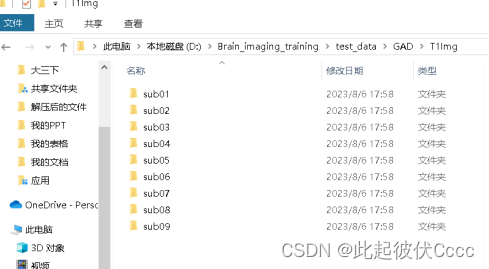

在与T1Raw相同文件夹的T1Img文件中生成了图像格式转换后的.nii文件,如下图所示: